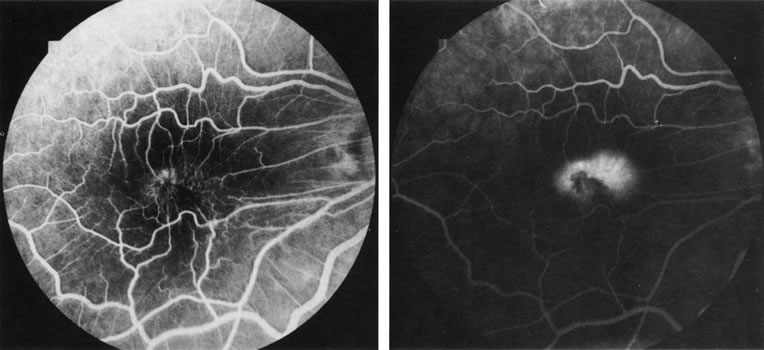

Central serous chorioretinopathy (CSC) is characterized by breakdown of the outer retinal barrier, with leakage of fluid through a defect in the retinal pigment epithelium into the subretinal space, resulting in a serous neurosensory detachment.78–205 The ophthalmologist can usually diagnose CSC based on the clinical examination and demographic information.93–95 Most patients with CSC are middle-aged men74 who often have type A personalities.75, 96–104 CSC has also been associated to the use of corticosteroids,105–118 pregnancy,119–126 increased adrenaline level and stress,127–132 hemodialysis,133,134 collagen vascular diseases,135–147 and hypertension.148–157 CSC typically presents as a large serous detachment in the posterior pole without an obvious source of the subretinal fluid.76 However, because a small CNV cannot be ruled out, FA is usually done to confirm the diagnosis. Characteristically, there is a small RPE defect, which hyperfluoresces early, and then there is slow filling of the overlying neurosensory detachment, which may have a classic “smokestack” (Fig. 21) or “ink blot” (Fig. 22) appearance.158–161 Occasionally, FA demonstrates multiple sites of leakage (Figs. 23, 24, and 25). FA sometimes fails to distinguish CSC from CNV readily because fibrinous subretinal precipitates can cause slow filling of the RPE detachment, which is suggestive of CNV (Fig. 26). Sometimes peripapillary PCV can cause a neurosensory macular detachment masquerading as CSC (Fig. 27).77

Fig. 21. Central serous chorioretinopathy. A. There is a central retinal pigment epithelium (RPE) detachment with linear RPE hyperplasia in a “hot-cross bun” configuration, indicating that the RPE detachment is chronic. B. This late fluorescein photograph illustrates leakage of fluorescein into the neurosensory detachment, with a classic “smokestack” formation.

Fig. 22. Central serous chorioretinopathy. A. In this arterial-phase photograph, a small area of early hyperfluorescence represents a small RPE detachment in the inferotemporal macula. B. This mid-phase photograph reveals increased fluorescence in the area, reflecting filling of a neurosensory detachment. C. The detachment continues to fill with fluorescence in this late-phase photograph. This gradually enlarging fluorescence is sometimes called “ink blot” filling of the subretinal space. (Courtesy of Dr. Kenneth G. Noble.)